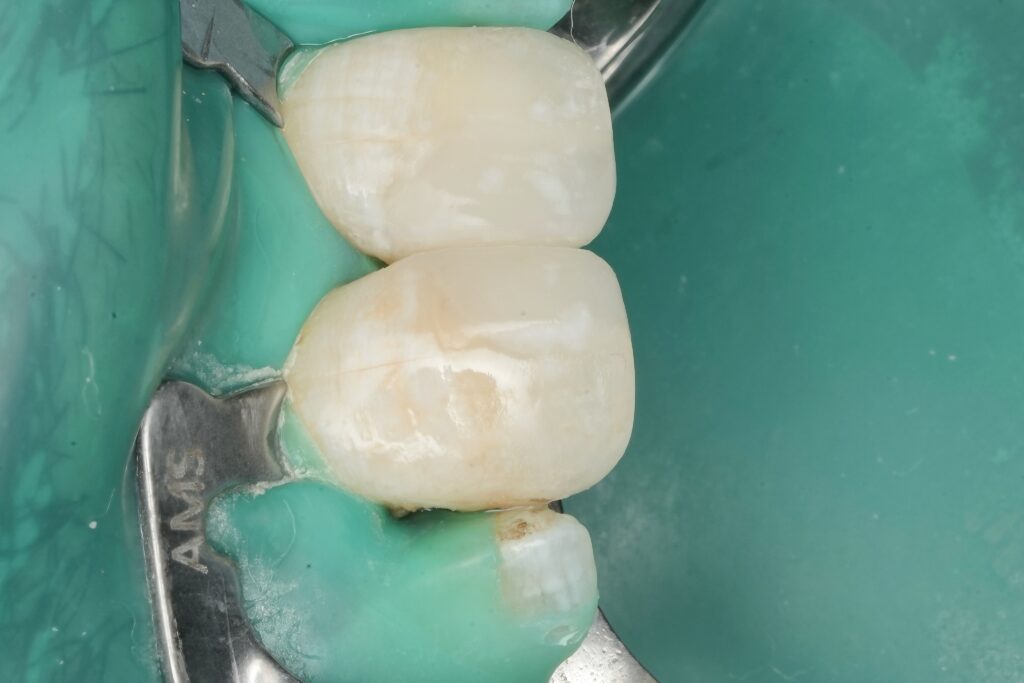

5) Matrixing: sectional matrix + ring = anatomy, not “a wall”

A sectional matrix system with a separation ring was used to rebuild:

- a tight contact

- correct emergence profile

- proper proximal convexity

Non-negotiable checks before curing the wall:

- wedge fully seated, no rocking

- matrix burnished at contact zone

- ring stable and not distorting the band

References: Loomans et al.; El-Mowafy et al.